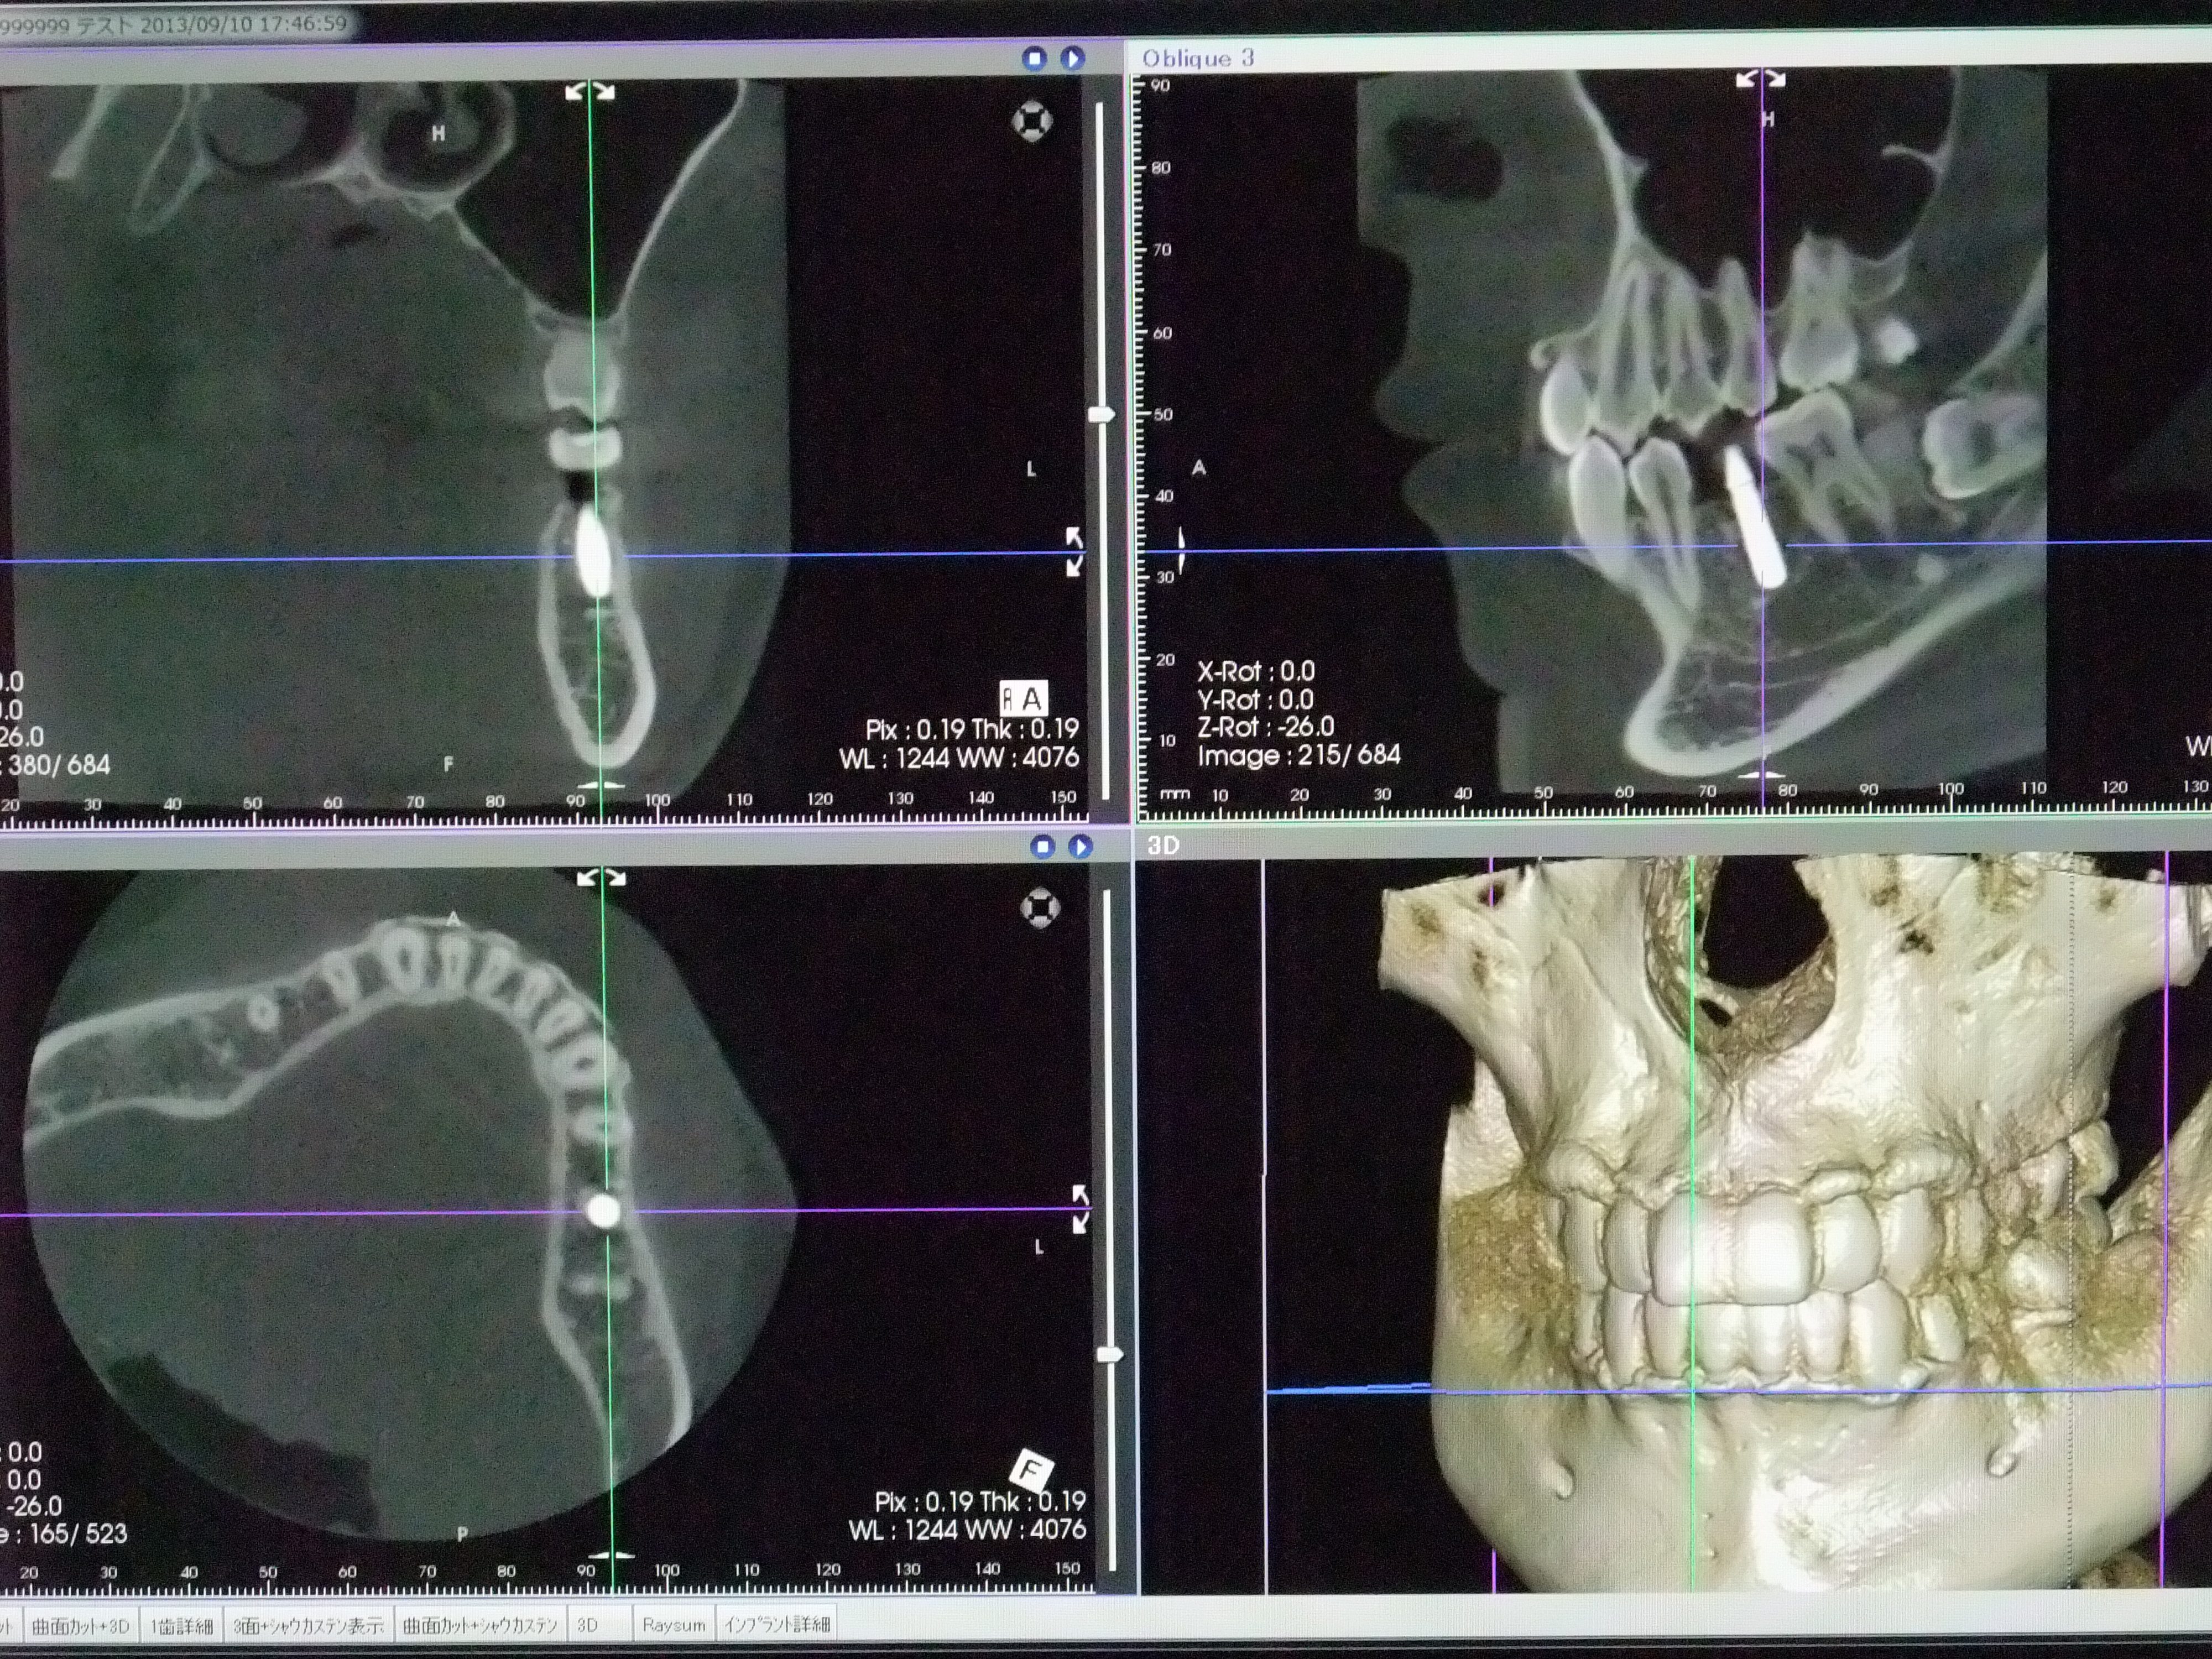

当院ではCTを完備しています。(朝日レントゲン工業製 AUGESOLIO)

CTの撮影装置              写真は院長のアゴに埋まってるインプラントです。

従来の2次元的なレントゲン写真では見えなかったものや見落とされていたものもが、

より精細で見やすい3次元のCTスキャンによって、正確な診査、診断ができるようになりました。